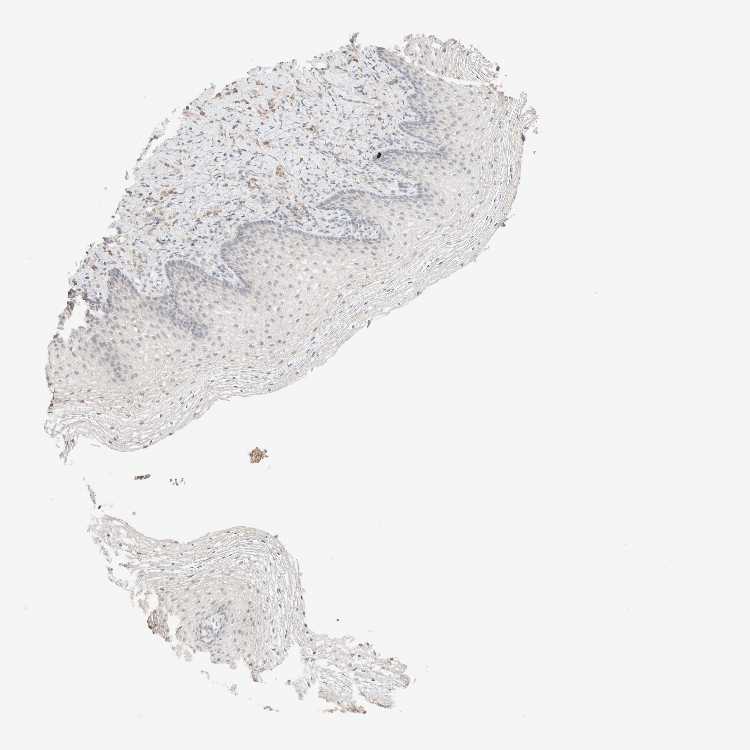

VAGINA - Antibody stainingi

Antibody staining in the annotated cell types in the current human tissue is reported as not detected, low, medium, or high, based on conventional immunohistochemistry profiling in selected tissues. This score is based on the combination of the staining intensity and fraction of stained cells.

Each image is clickable and will lead to virtual microscopy that enables deeper exploration of all samples and also displays staining intensity scores, fraction scores and subcellular localization as well as patient and tissue information for each sample.

Antibody HPA021836Antibody HPA052215Antibody CAB025197

Squamous epithelial cells LowNot detectedNot detected